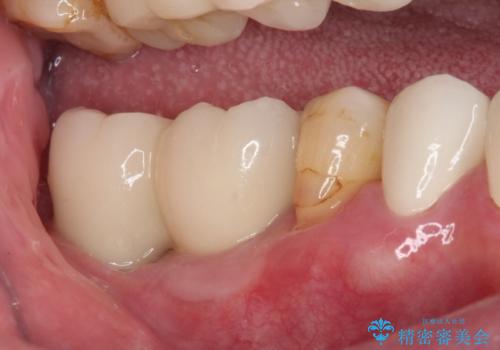

憧れの白い歯に 全顎セラミック治療

- 60歳を越え、黄ばんだ前歯をセラミッククラウンできれいな口元にしたいとのことで来院された患者様です。

診察したところ、前歯は反対咬合であり、その影響で抜歯が必要な奥歯があることが分かりました。

抜歯が必要な奥歯は、インプラント並びにブリッジにより補綴を行い、上下前歯は反対咬合を改善させるように補綴治療を行うこととしました。

健全な歯を削ってセラミッククラウンに置き換えることは、本来避けるべき治療と考えますが、今回は①患者様が60歳を越えていること、②要改善の咬合により抜歯が必要な奥歯があること、③反対咬合の前歯改善の手段としてセラミック治療が選択肢にあることなどから、全顎的なセラミック治療を行うこととしました。